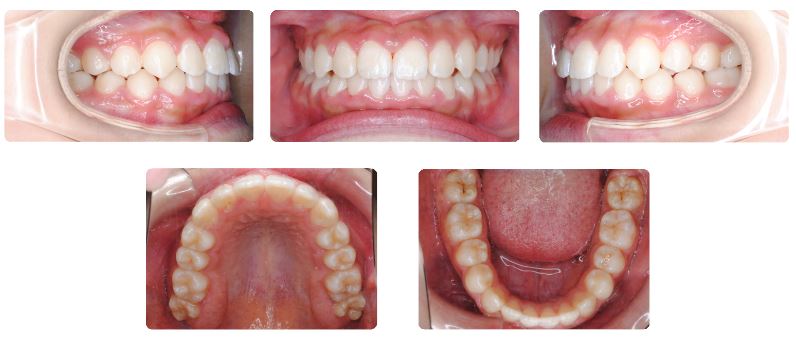

治療期間:2年4ヶ月

上あごの12才臼歯である第二大臼歯が生えてくるまで時間がかかったこと、上あごの奥行きがやや足りないため生え始めた際に頬側に向かい交叉咬合になってしまい、この噛み合わせの改善のために2年4か月を要しました。